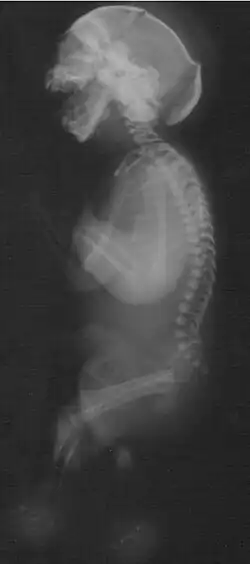

Neu–Laxova syndrome (NLS, also known as Neu syndrome; Neu-Povýsilová syndrome; or 3-phosphoglycerate dehydrogenase deficiency, neonate form)[2] is a rare autosomal recessive disorder characterized by severe intrauterine growth restriction and multiple congenital malformations. Neu–Laxova syndrome is a very severe disorder, leading to stillbirth or death shortly after birth. It was first described by Dr. Richard Neu in 1971[3] and Dr. Renata Laxova in 1972[4] as a lethal disorder in siblings with multiple malformations. Neu–Laxova syndrome is an extremely rare disorder with fewer than 100 cases reported in medical literature.

Neu-Laxova syndrome presents with severe malformations leading to prenatal or neonatal death. Typically, NLS involves characteristic facial features, decreased fetal movements and skin abnormalities.[5] Fetuses or newborns with Neu–Laxova syndrome have typical facial characteristics which include proptosis (bulging eyes) with eyelid malformations, nose malformations, round and gaping mouth, micrognathia (small jaw) and low set or malformed ears. Additional facial malformations may be present, such as cleft lip or cleft palate. Limb malformations are common and involve the fingers (syndactyly), hands, or feet. Additionally, edema and flexion deformities are often present. Other features of NLS are severe intrauterine growth restriction, skin abnormalities (ichthyosis and hyperkeratosis) and decreased movement. Malformations in the central nervous system are frequent and may include microcephaly, lissencephaly or microgyria, hypoplasia of the cerebellum and agenesis of the corpus callosum. Other malformations may also be present, such as neural tube defects.